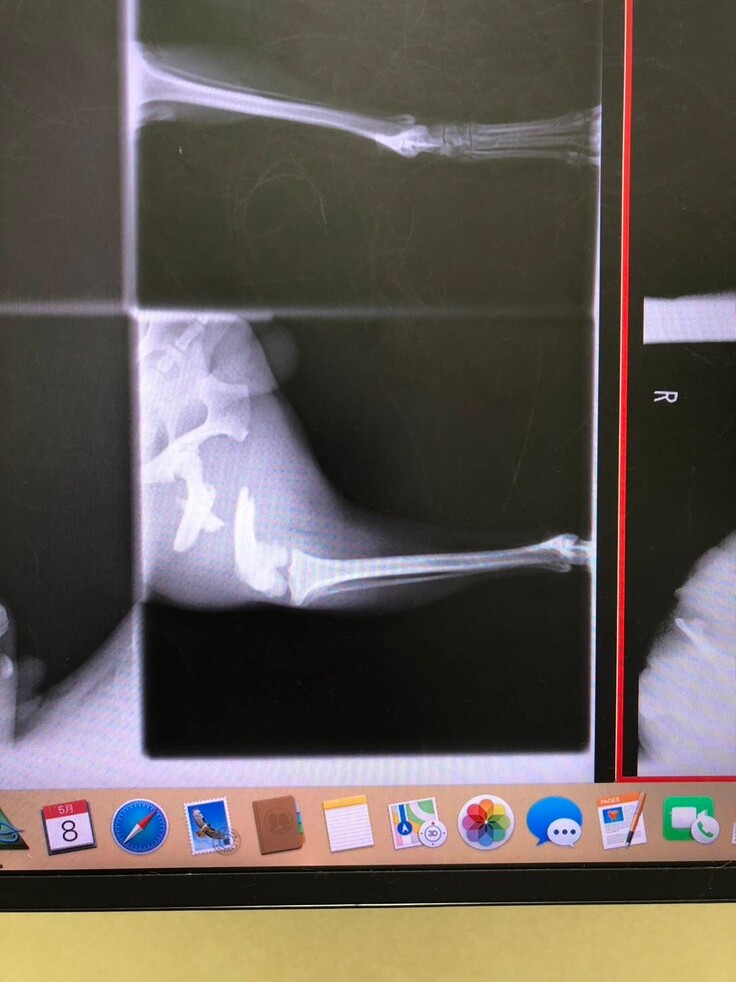

5月8日・病院でレントゲンを撮ってもらうと、右後脚大腿部が3か所複雑骨折をしていることが判明しました。かなり難しい手術になること、費用も高額になることの説明を受けました。

●5/8(初診)2,310円 写真①

●5/10からの医療費(2回の手術費用込)397,650円 写真②

写真② 5/10からの医療費の領収書と明細書(2回の手術費用込)397,650円